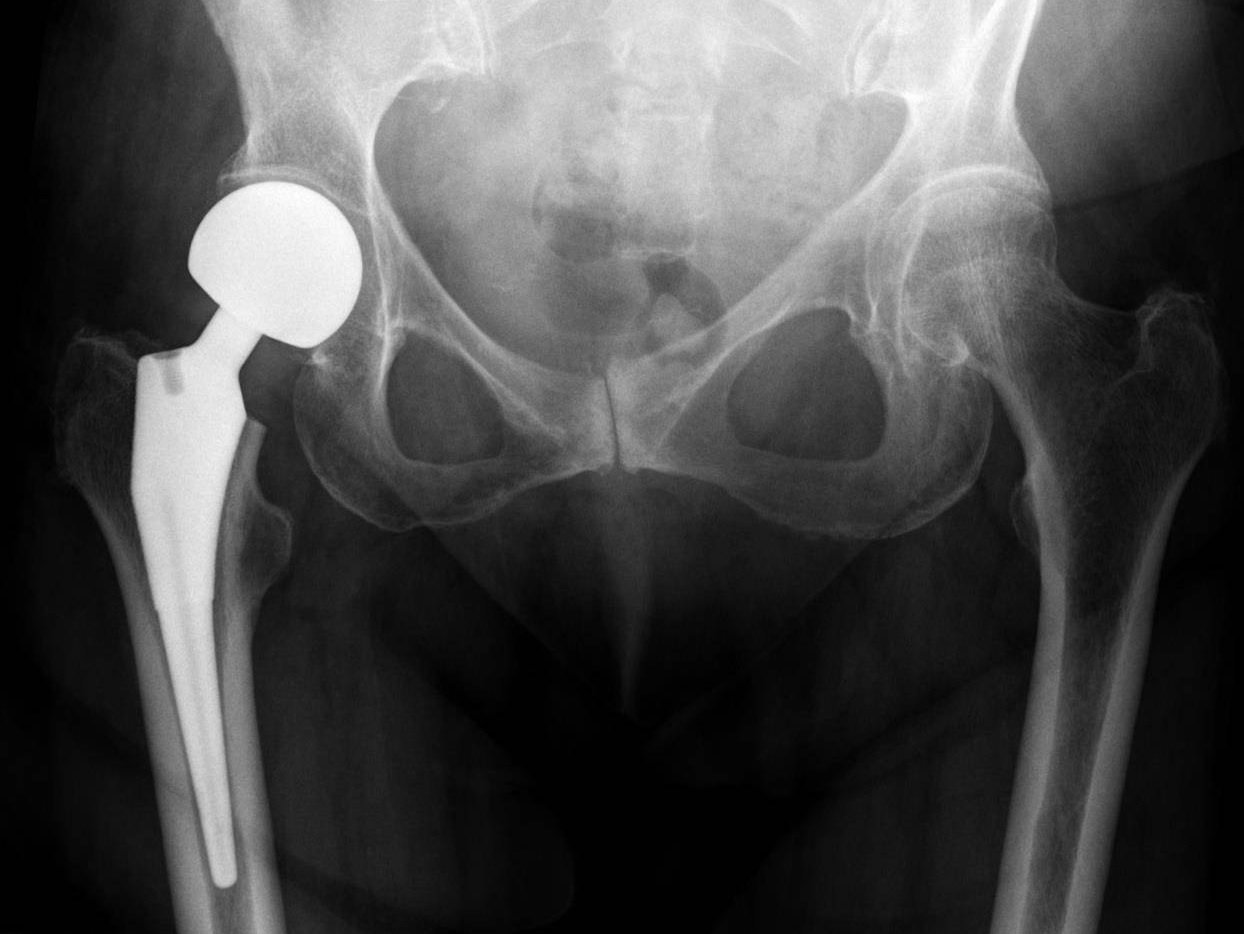

Understanding Hip Replacement Surgery: What It Is, What to Expect & How Recovery Really Looks

Hip Replacement Surgery: How Modern Techniques and New Technology Are Changing the Way We Restore Movement